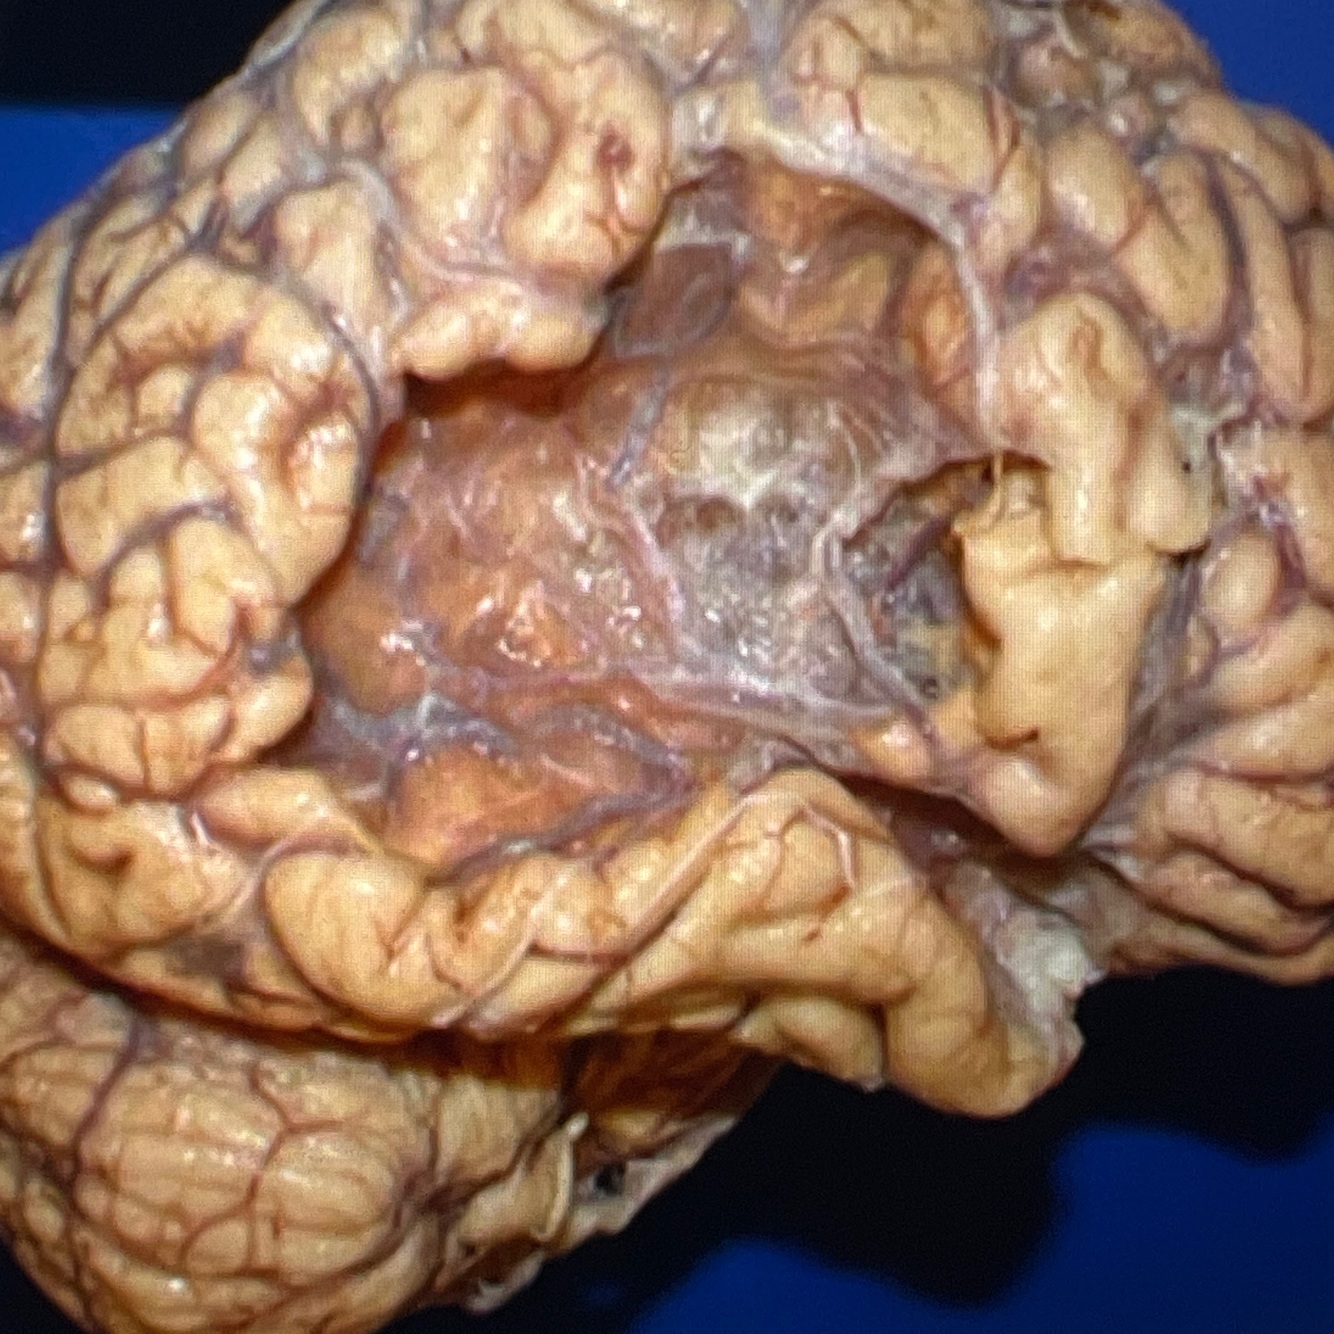

Diagnosis: subarachnoid hemorrhage

Location: subarachnoid space

A whole brain showing blood collection in the subarachnoid space, covering the inferior surface of the brain